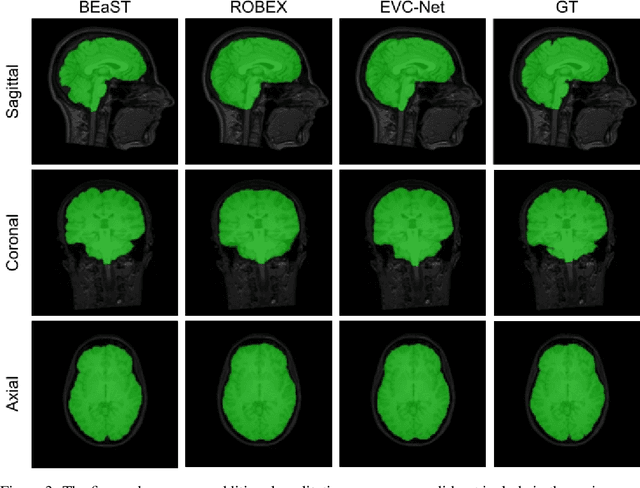

Abstract:Brain extraction is one of the first steps of pre-processing 3D brain MRI data. It is a prerequisite for any forthcoming brain imaging analyses. However, it is not a simple segmentation problem due to the complex structure of the brain and human head. Although multiple solutions have been proposed in the literature, we are still far from having truly robust methods. While previous methods have used machine learning with structural/geometric priors, with the development of deep learning in computer vision tasks, there has been an increase in proposed convolutional neural network architectures for this semantic segmentation task. Yet, most models focus on improving the training data and loss functions with little change in the architecture. In this paper, we propose a novel architecture we call EVC-Net. EVC-Net adds lower scale inputs on each encoder block. This enhances the multi-scale scheme of the V-Net architecture, hence increasing the efficiency of the model. Conditional Random Fields, a popular approach for image segmentation before the deep learning era, are re-introduced here as an additional step for refining the network's output to capture fine-grained results in segmentation. We compare our model to state-of-the-art methods such as HD-BET, Synthstrip and brainy. Results show that even with limited training resources, EVC-Net achieves higher Dice Coefficient and Jaccard Index along with lower surface distance.